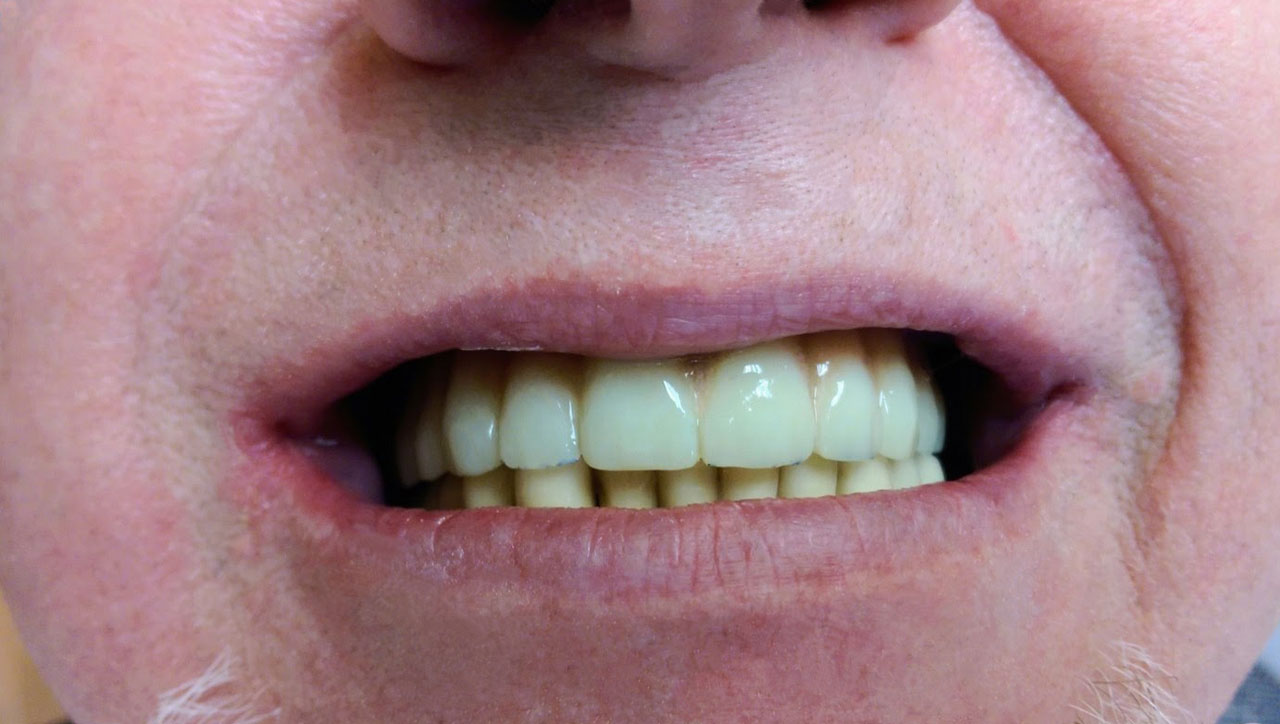

• esettanulmany-32

72 órávan a felső állcsont teljes implantációs helyreállítása után, így mosolyog a páciens a beragasztott, fix hiddal.